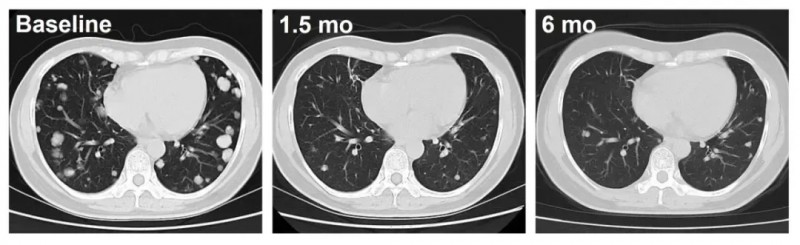

▼C010号患者治疗前后影像学对比

具体来看,C010号患者(DL3)的疗效更为持久,经12个月以上跟踪,肿瘤持续稳定缩小;另一例C023号患者(DL4)治疗仅1.5个月,肺转移病灶便出现深度应答,影像学可见肿瘤显著缩小。

2024年美国临床肿瘤学会(ASCO)年会上,西比曼生物公布了C-CAR031首次人体临床研究(IIT)的惊艳数据。针对先前接受1-6线治疗的多线治疗失败晚期肝癌(HCC)患者,该疗法展现出可控的安全性与显著的抗肿瘤活性。其中两例患者(C023与C010)接受治疗后,均呈现肿瘤持续退缩的振奋疗效。

CAR-T细胞疗法除了治疗血液肿瘤外,近年来也被尝试用于实体瘤领域。比如C-CAR031就是一款靶向GPC3(肝癌黄金靶标)的CAR-T细胞疗法,由阿斯利康基于其TGFβRII(转化生长因子-β受体II)显性负装甲发现平台设计,西比曼生物负责中国地区的生产并联合开发。其核心优势在于双重靶向机制:一方面特异性结合肝癌、肺癌等实体瘤高表达的GPC3;另一方面搭载TGFβ信号通路阻断“分子盾”,可突破肿瘤微环境的免疫抑制。